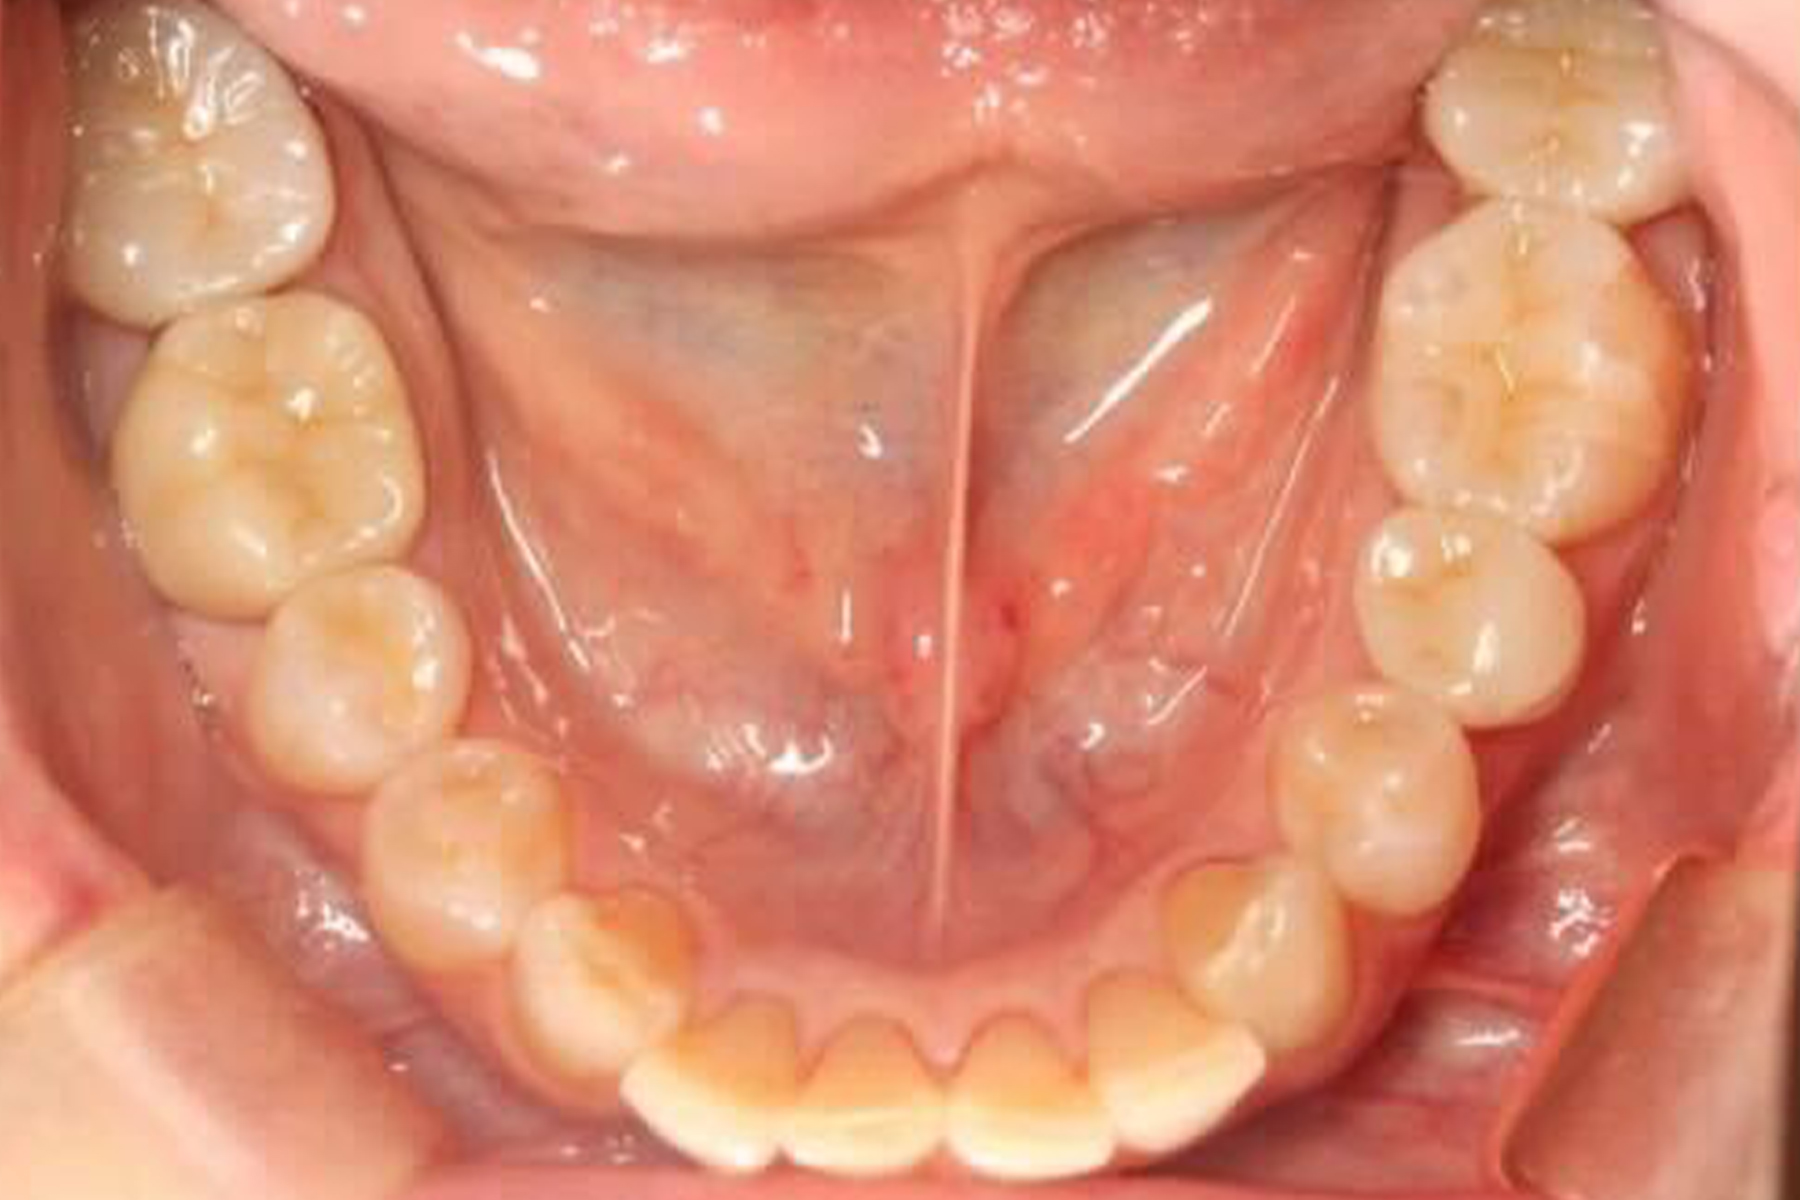

AFTER

| 主訴 | 銀歯を白い歯に変えたい |